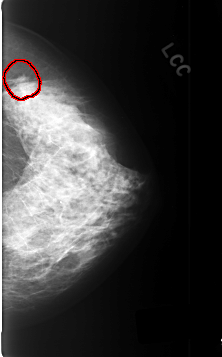

C_0358_1.LEFT_CC

FILE: C_0358_1.LEFT_CC.OVERLAY

TOTAL_ABNORMALITIES 1

ABNORMALITY 1

LESION_TYPE MASS SHAPE IRREGULAR MARGINS OBSCURED

ASSESSMENT 5

SUBTLETY 3

PATHOLOGY MALIGNANT

TOTAL_OUTLINES 1

BOUNDARY